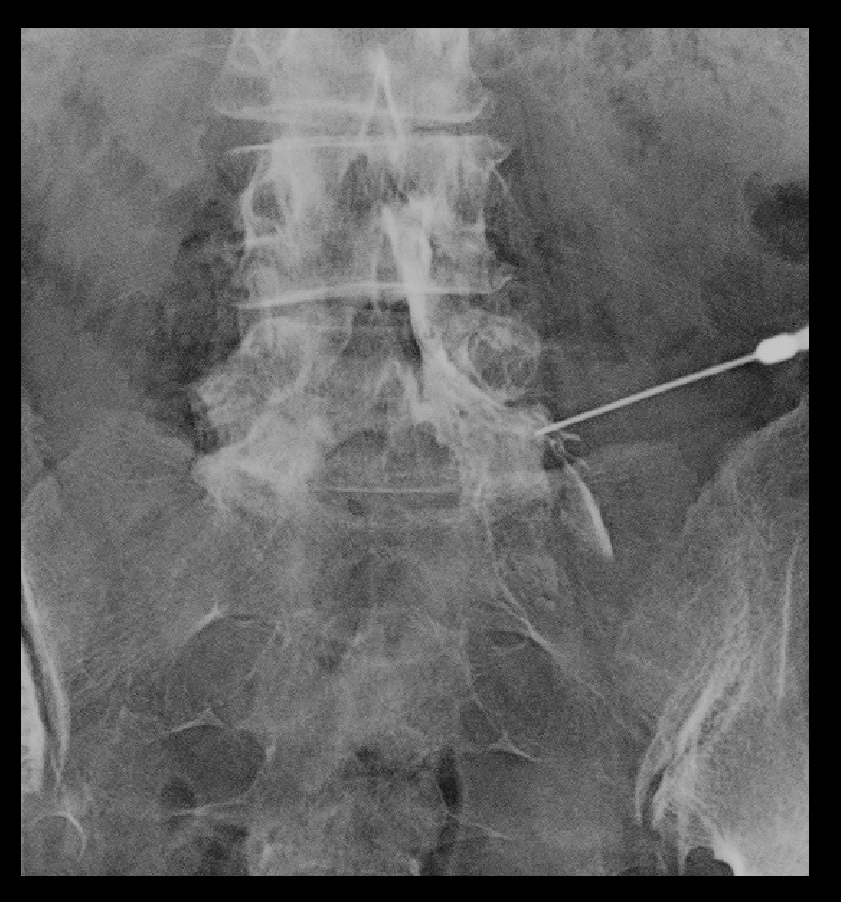

70才女 就眠時RB.jpg

1週間後の3月8日痛みはVAS6→0に軽減しました。